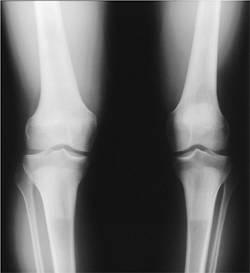

![]() |

|

FIGURE 15-33

Hypovitaminosis C in a 10-month-old. Radiographs of the knees showing ringed epiphyses and metaphyseal condensation with fractures (arrows) proximally. |